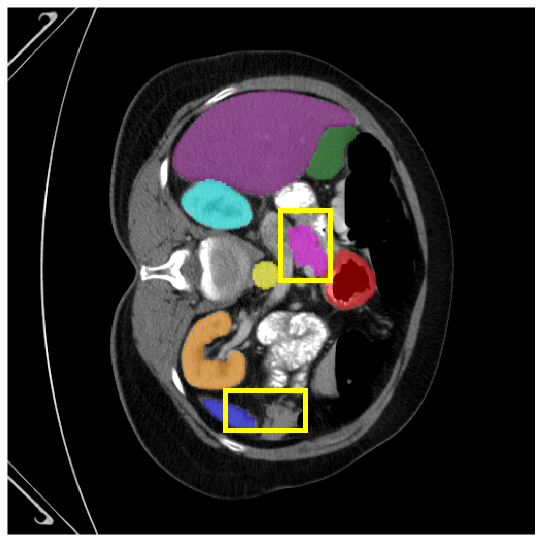

4.3.2 Visual Comparisons

Visualization of our method on the Synapse and ACDC datasets is shown in Fig. 3(a) and Fig. 3(b). For the Synapse dataset illustrated in Fig. 3(a), FCT failed to accurately segment SM and GB, while MERIT achieved precise segmentation of SM but struggled with GB. In contrast, our method achieved accurate segmentation of both SM and GB. Regarding the ACDC dataset shown in Fig. 3(b), while previous methods achieve comparable segmentation of the Myo and LV to the GT, they exhibit noticeable errors on the RV, including invasion into adjacent organs and misrecognition. On the other hand, our method accurately segments across all three structures Myo, LV, and RV, performing as precisely as the GT. We demonstrate the superiority of our method quantitatively and qualitatively.

To demonstrate the superiority of our method, additional qualitative comparison results for the ACDC and Synapse datasets are presented in Fig. 6, Fig. 7, respectively. Notably, in the case of GB, the quantitative results in Fig. 7 show relatively lower performance in ‘only ’. However, the visualization results in Fig. 7 reveal instances where the enhanced images identified GB regions that the original images failed to segment, albeit with some boundary over-segmentation. In such scenarios, our proposed method successfully leveraged the information from enhanced images to achieve more accurate GB segmentation. Note that this finding underscores the fact that even when quantitative performance metrics appear lower, the additional information provided by enhanced images can be valuable in the actual segmentation process.